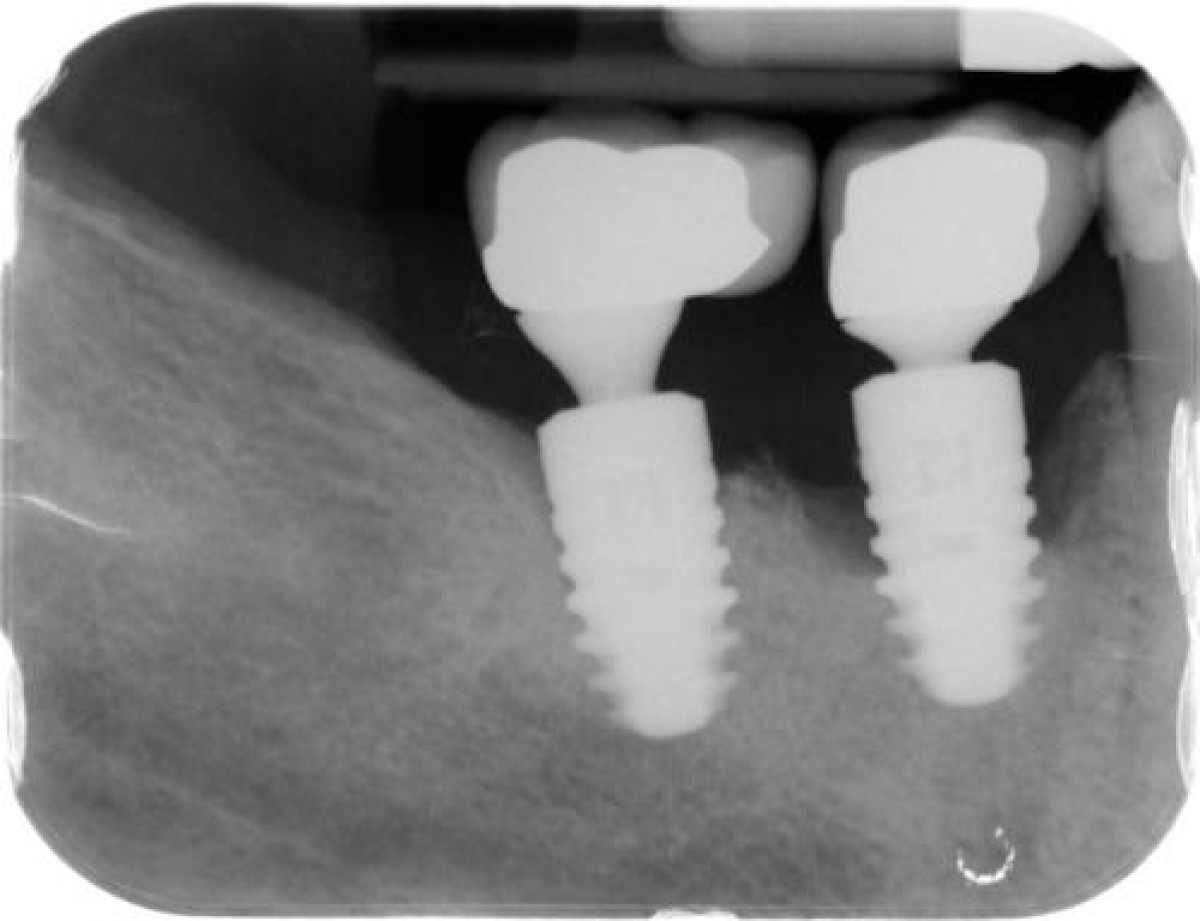

Smoking, type 2 diabetes mellitic and peri-implantitis

In a 7-year follow-up clinical observational study, published on Journal of Periodontology September 2020, the authors evaluated the survival of dental implants in CS smoking patients and NS non smoking patients with type 2 diabetes mellitic (T2DM) and not.

The PI plaque index, the BOP bleeding index, the PD pocket depth and the CBL crestal bone level were measured in all patients included in the study. Statistical analysis was performed using analysis of variance.

Peri-implant PI (P <0.01), PD (P <0.01), and CBL (P <0.01) were significantly higher among CS and NS with T2DM and CS without T2DM than NS without T2DM. Peri-implant BOP was significantly higher among CS and NS with T2DM than CS and NS without T2DM (P <0.01).

From the data of this study, which must be confirmed in other similar studies, it can be concluded that peri-implant inflammatory variables are worse in CS smokers and in non smokers NS with T2DM type 2 diabetes mellitic compared to us NS smokers without diabetes mellitic 2 T2DM.